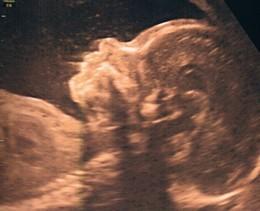

Déjà l'essentiel : ma PUCE va bien, oui, la deuxième dans mon bidon. C'est confirmé, une petite soeur pour Mélina, on est super contents !

Un beau petit bébé qui suit les traces de Mélina avec à peu près les mêmes mensurations... 525 grammes, c'est le chiffre que j'ai retenu. Evidemment, 10

doigts, 10 orteils, 2 oreilles, 1 bouche qui faisait la moue d'ailleurs.... tout ça aussi c'est ok.